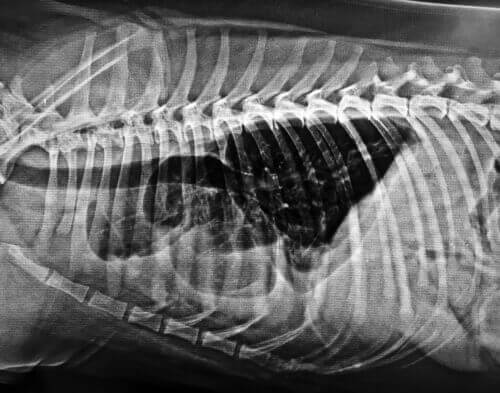

Doença cardiovascular

Foi demonstrado que os níveis de CoQ10 diminuem no coração de animais de estimação com doenças cardíacas. Assim, o uso mais comum de CoQ10 em cães é como um coadjuvante no tratamento da insuficiência cardíaca congestiva.

A coenzima Q10 é eficaz no tratamento da cardiomiopatia canina e condições relacionadas.